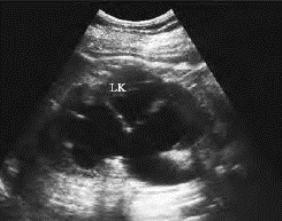

3.重度肾积水超声表现 肾脏增大,肾实质明显变薄,肾盂肾盏明显扩大,相邻肾盏互相交通,并与肾盂相通(图29-6)。

图29-6 重度肾积水声像图

肾脏增大,肾盂肾盏明显扩大并相通